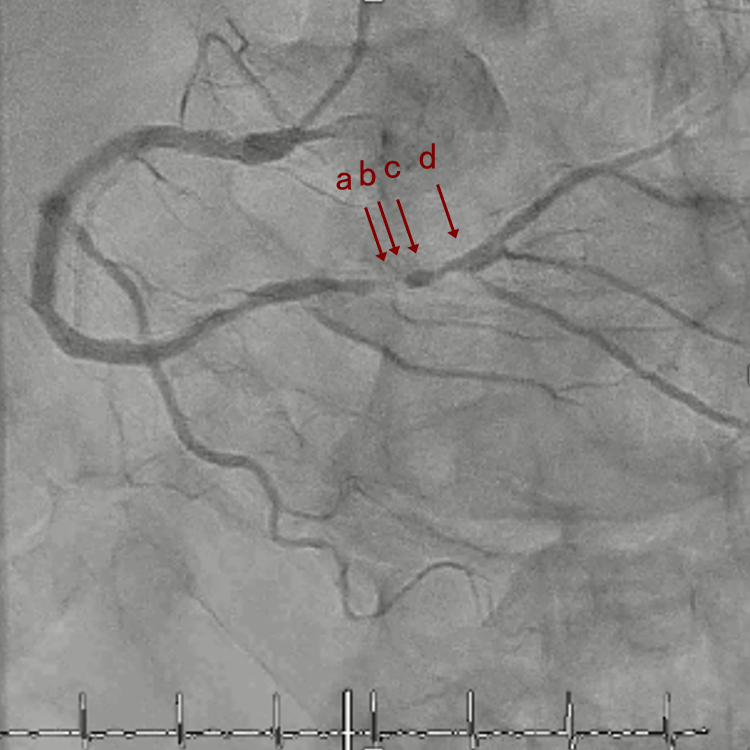

CAG

RCA distalの高度石灰化狭窄病変

OAS low speedによる引きを赤線の区間行う方針とした。

OAS low3回 造影上の切削区間の確認